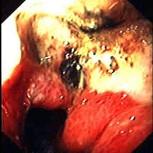

问题 患者,男,50岁,反复上腹痛1年入院。查体:心肺腹未见异常。电子胃镜结果如图,诊断为 ( )

选项 A.胃癌 B.胃淋巴瘤 C.胃溃疡 D.胃溃疡并真菌感染 E.胃憩室

答案 A